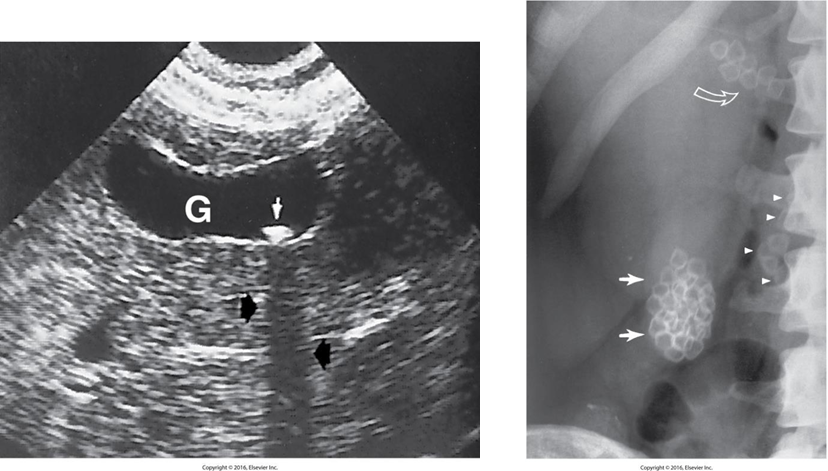

Cholelithiasis (Gallstones)

Stones found in the gallbladder

Two major types of ____:

Cholesterol – predominant type

Pigment

Radiological Appearance:

Acute Cholecystitis

is acute inflammation of the gallbladder.

It is usually caused by cystic duct obstruction by a gallstone.

Thickened gallbladders walls (>3mm)

Chronic Cholecystitis

Result of numerous attacks of acute cholecystitis with subsequent fibrosis of the gallbladder wall.

Clinically, patients may have some transient RUQ pain but not the tenderness as experienced with acute cholecystitis.